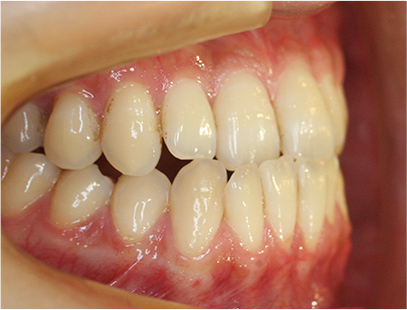

症例01|中学生の男子

前歯部の反対咬合

前歯部の反対咬合と上顎前歯のデコボコを主訴として来院されました。精査、診断の結果「前歯部に叢生を伴う反対咬合」と診断されました。

治療計画

非抜歯にて前歯の再配列、反対咬合の改善を行う事にしました。

治療前の写真と比べると前歯部の反対咬合は改善されて、上顎の前歯部のデコボコも綺麗に並べる事ができました。

また口元は上の歯が前に出たために口唇がへこんでいたことも改善されて男らしい綺麗な口元に改善できました。 治療期間は2年と6か月を必要としました。